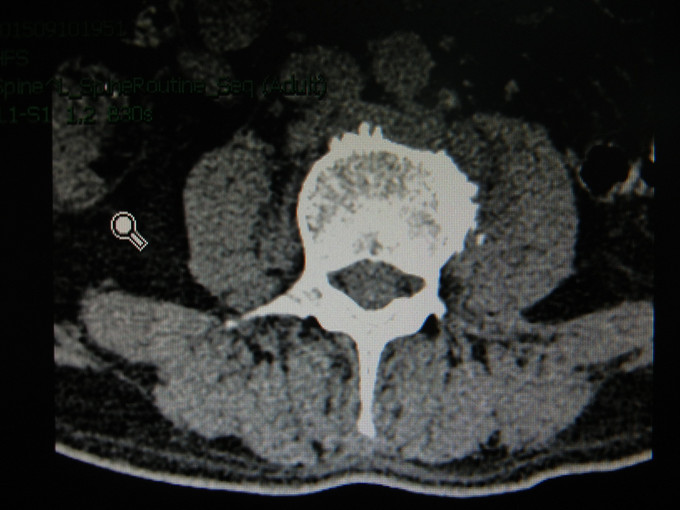

患者男,56岁。因“发热伴腰部疼痛3月”入院。现病史:患者于2015年6月中旬无明显诱因出现发热,体温多波动在37-38度之间,最高38.5摄氏度,下午为主,伴下肢关节疼痛。无鼻塞、流涕、喷嚏、咳嗽、咳痰、头痛、头晕、腹痛、腹泻等,以感冒给予治疗后症状无好转,7月中旬到当地医院就诊,考虑为布鲁氏菌感染,给予利福平4片/次,1次/日,多西环素1片/次,2次/日及相关治疗,症状无明显好转,后就诊我院,予以抗感染、退热及对症支持等治疗,确诊为“腰椎结核”后出院行抗结核治疗半月,门诊以“腰椎脓肿”收入我科。起病以来患者一般情况良好。

查体:生命体征平稳,心肺腹体检未见明显异常。专科情况无特殊。 辅助检查:MRI示腰椎椎体边缘骨质浓密、增生,部分骨赘骨桥形成。L2-5椎体及椎旁见不规则软组织密度影,与双侧腰大肌分界不清,结合病史符合感染性病变,结核可能性大;

诊断:腰椎结核。 治疗:全麻下行腰椎结核病灶清除术+内固定术。